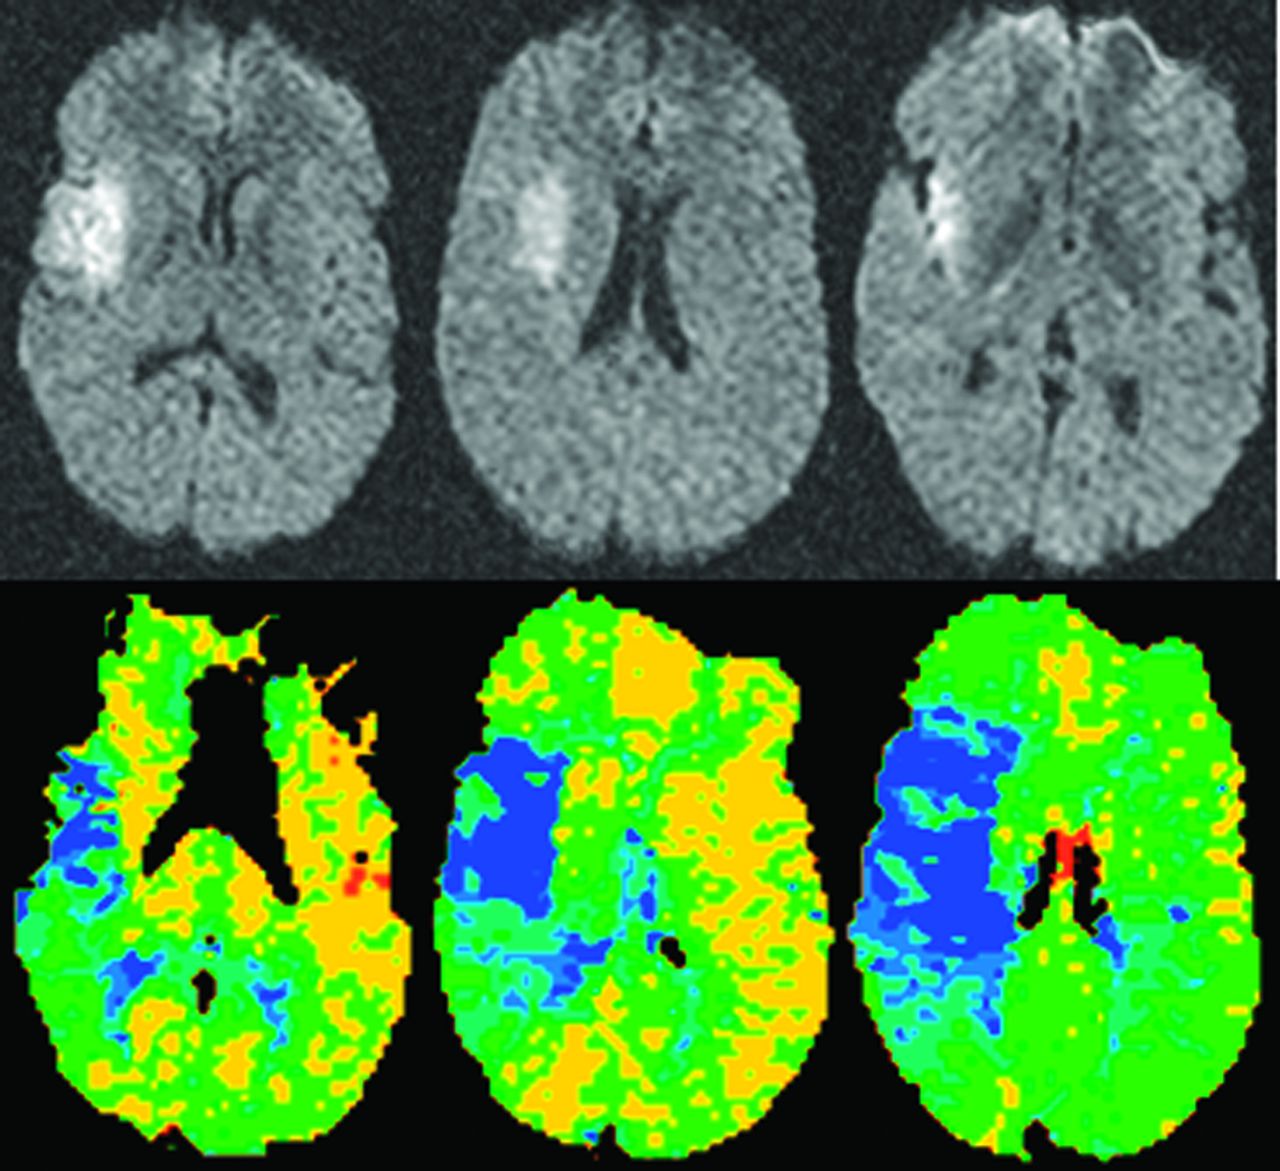

Diffusion-weighted成像(驾车)和perfusion-weighted MRI(预警指示器)是广泛使用的核磁共振成像模式,提供有价值的信息焦点脑缺血的组织特点和流动的微循环。17异常的表观扩散系数(ADC)在缺血性脑区醉酒驾车和组织灌注在预警指示器开始后的几分钟内可检测缺血中风动物模型和在大多数中风病人当他们最初成像。此信息明显有利于中风的诊断和定位,但它也可能提供洞察潜在可逆缺血组织的存在和大小。最初提出,缺血性脑区与灌注减少预警指示器和hyperintensity醉酒驾车梗塞的代表地区,地区异常灌注正常的驾车代表半影。18这种所谓的DWI-PWI不匹配是临床上有用的但只有接近梗塞核心之间的区别和半影(图1)。预警指示器异常的一部分代表oligemic组织CBF减少的严重程度相对温和,和这个组织不会成为不可逆转地受伤。19醉酒驾车的相反,部分异常与相对温和的ADC与及时的再灌注可以扭转下降,已经证明了实验中风模型和中风患者接受静脉和动脉内的溶栓治疗。20.,21DWI-PWI不匹配的识别的一个重要变量是2的区域异常是如何确定的。醉酒驾车的损伤识别是相对简单的地区hyperintensity ADC值相应减少。描述异常的预警指示器地区更多的问题,因为它是依赖于阈值用于定义hypoperfused组织。22目前,没有有效的,普遍商定的阈值定义预警指示器异常,已经和建议使用的地图时间达到峰值,平均运输时间(MTT)、最大浓度和时间(T马克斯)定义预警指示器灌注不足。最合适的和精确的验证预警指示器hypoperfused组织的鉴定还有待建立。目前,MTT和T马克斯方法是使用最广泛的,尽管精确验证它们允许临床医生合理识别异常预警指示器区域之间的明显不匹配和醉酒驾车hyperintense区域。

在实验中风研究自然历史和治疗对DWI-PWI不匹配的演变的影响进行评估。在实验中使用验证阈值来确定扩散和灌注损伤卷,不匹配的演变在老鼠缝合闭塞和栓塞性中风模型演示了一个更大、更持久的插子的模型不匹配。23这表明,插子的模型更接近于人类中风的病理生理学缝合模型和有更多的潜在可挽回的缺血性组织可能适合治疗更长的时间。治疗实验表明,粒细胞集落刺激因子开始1小时后中风发作的永久闭塞缝合模型停止酒后驾车的扩大,维护DWI-PWI错配数小时,并降低组织学证实梗塞的范围在24小时。24在栓塞大鼠中风模型中,高速流normobaric氧过多也停止了醉酒驾车病变增大,当结合静脉组织纤溶酶原激活物(tPA)在中风发作后3小时,它允许这种疗法显著减少梗死体积与对照组相比在24小时(室内空气和tPA 3小时)。25描述的使用绝对的ADC值和定量CBF测量动脉spin-labeling预警指示器似乎更精确的比与丸对比预警指示器的相对简单的方法。随着这种预警指示器技术变得可供人类中风成像,类似的方法更精确的界限不明的识别可能会进化。